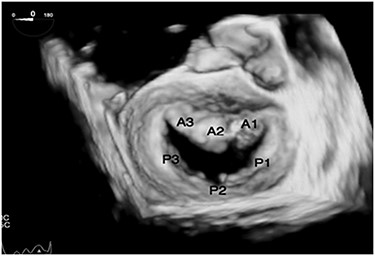

TEE views in a patient with dextrocardia with SI are different than the standard views. In the midesophageal four-chamber view at 0°, the right atrium and the right ventricle are on the right side of the display (Fig. 2A). The midesophageal two-chamber view, usually obtained at a multiplane angle of 90°, is identical to the view seen in a patient with situs solitus (Fig. 2B). The midesophageal aortic valve long-axis view (LAX) was obtained at a multiplane angle of 30–40° (Fig. 2C), while the midesophageal aortic valve short-axis view (SAX) was obtained at a multiplane angle of 120–130° (Fig. 2D). The midesophageal Bicaval view was obtained at 76° (Fig. 2E). The transgastric mid-papillary SAX was obtained as expected at 0° but with the right ventricle on the right side of the display (Fig. 2F). So in summary, TEE views in dextrocardia patients are similar to situs solitus patients at a multiplane angle of 90°, they are mirror images of each other at 0°, while the aortic valve SAX and LAXs are “flipped” in comparison with situs solitus patients. The approach to mitral valve assessment with TEE must be altered [10]. Firstly, the multiplane angles required to assess different parts of the mitral valve leaflets are different. Secondly, when examining the valve using 2D TEE in the midesophageal aortic valve with LAX view in a dextrocardia patient, a leftward rotation of the TEE probe will examine the posterior portion of the valve (A3/P3) while in a situs solitus patient, such a leftward rotation would result in the anterior parts of the valve to be examined (A1/P1). This point is important when discussing mitral valve repairs or the position of paravalvular leaks. If the surgeon stands on the left side of the patient, then the surgical view of the mitral valve will be as shown in Fig. 3.

A: Midesophageal four-chamber view at 0°. B: Midesophageal two-chamber view at 90°. C: Midesophageal aortic valve LAX at 30°. D: Midesophageal aortic valve SAX at 120°. E: Midesophageal bicaval view. F: Transgastric midpapillary short axis view at 0°.

Transesophageal echo 3D view of mitral valve in dextrocardia as viewed intraoperatively by the surgeon standing on the left side of the patient.